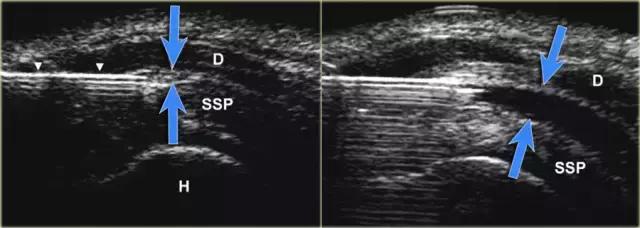

肩峰下滑囊

肩峰下 - 三角肌囊是滑膜内衬空间,其不包含可观察到的或仅很小量的流体。滑囊由两个法氏囊叶组成。 外侧和内侧叶分别与三角肌筋膜和肩袖融合。 滑囊叶可以容易地彼此滑动,从而便于肩部的运动范围。盲性肩峰下注射药物到肩峰下囊中是全科医生和矫形外科医生经常进行的治疗。 错过肩峰下囊肿的注射发生率为12%至70%。